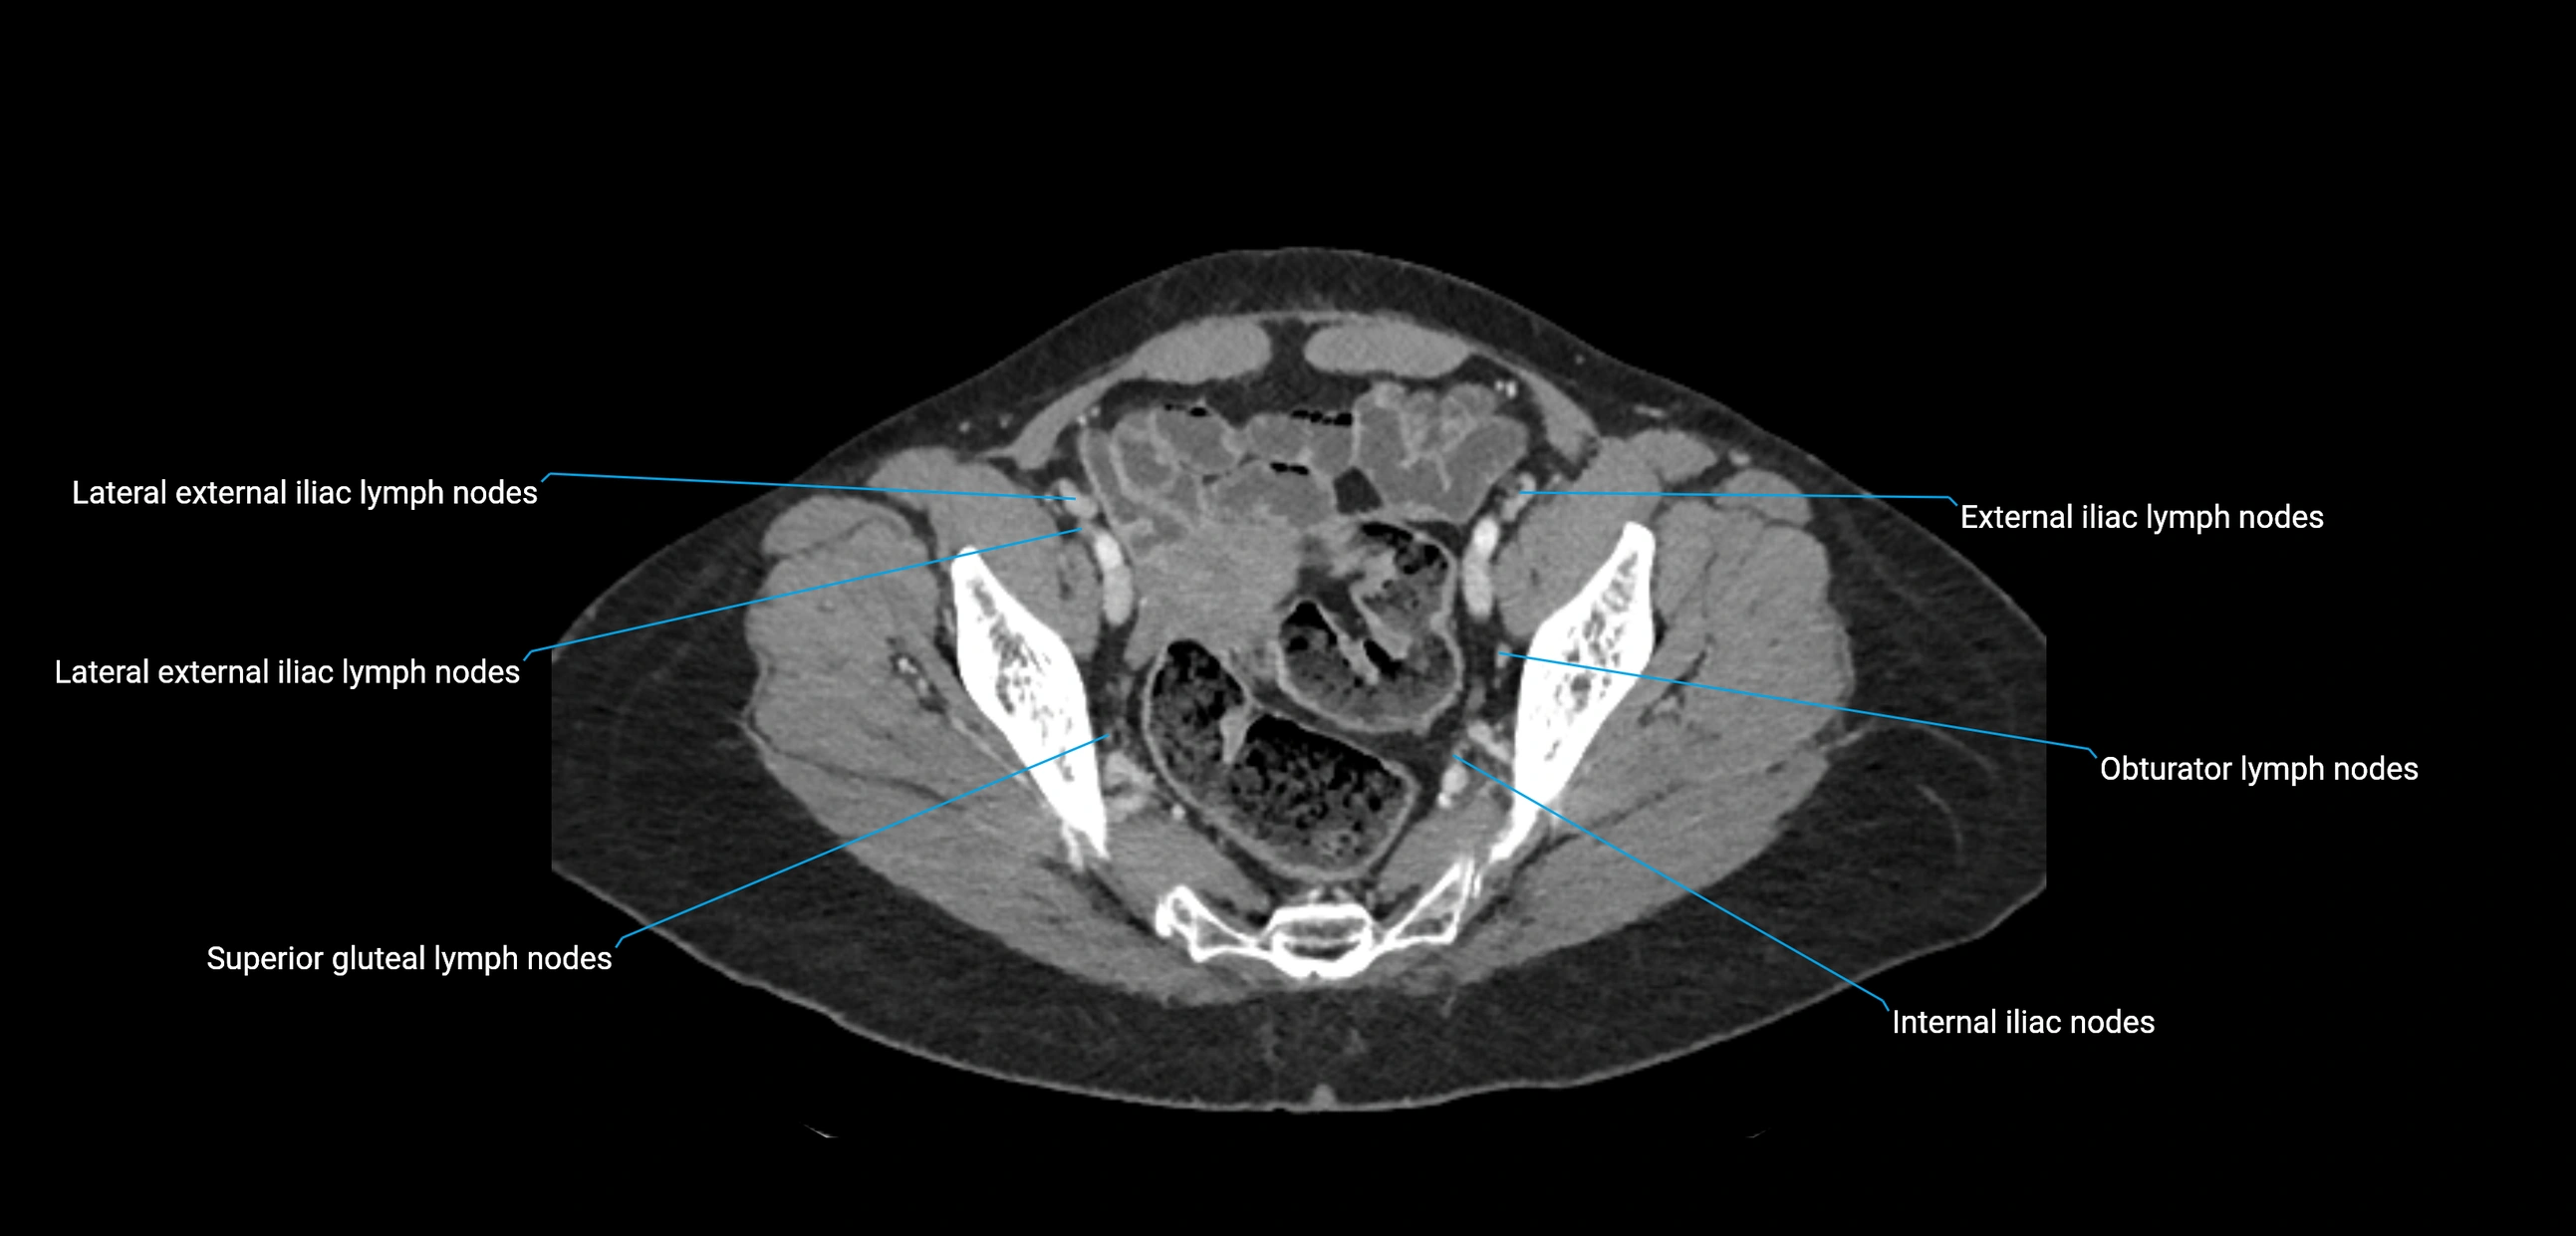

CT Appearance

CT Pre-Contrast:

• Nodes appear as soft-tissue density nodules adjacent to the aorta and IVC

• Calcification may be seen in chronic infections (e.g., tuberculosis)

CT Post-Contrast:

• Normal nodes enhance homogeneously

• Malignant nodes may show heterogeneous enhancement, central necrosis, or conglomerate formation

• Size >1 cm short axis is suspicious, though morphology and distribution are equally important

CT Venography (CTV):

• Demonstrates nodal encasement or compression of adjacent vessels (aorta, IVC, renal veins)

• Useful in staging testicular and ovarian malignancies

• Provides 3D reconstructions for retroperitoneal lymph node dissection planning